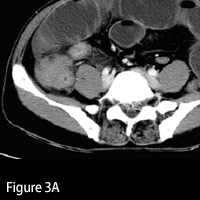

| Figure 3 — Axial image demonstrates focal “masslike†thickening of the cecum and associated involvement of the terminal ileum. | |

Multiplanar imaging of the abdomen/pelvis demonstrated multiple fluid-filled, dilated loops of small bowel, consistent with obstruction. No free intraperitoneal air or fluid was detected. Within the right lower quadrant, there was transmural, circumferential thickening of the proximal ascending colon and cecum. Prominent enhancement of the colonic mucosa at the point of obstruction was noted. A key finding was concomitant involvement of the terminal ileum. A mild degree of pericolonic and mesenteric fat stranding was visualized, compatible with regional inflammation. Multiple enlarged mesenteric lymph nodes were also appreciated.

Transmural involvement of the ileocecal valve region is fairly classic yet not specific for TB colitis. There may be a striking desmoplastic or fibrotic reaction at the site of infection. Occasionally, focal infection can assume a masslike appearance radiologically, heightening concern for malignancy (ie, carcinoma, lymphoma). Mucosal enhancement is generally the rule, with transverse ulceration seen upon endoscopic and pathologic evaluation. Similar to Crohn’s disease, fistulae and sinus tracts may develop secondarily, though less commonly.